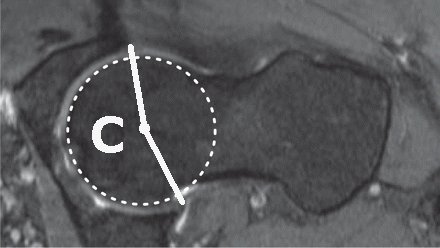

The range of movement before impingement is estimated from sectional images of the hip. A number of parameters have been measured, some completely different measurements have given the same Greek letter! Even reduced to two dimensions there are several parameters to consider:

Notes Clin Orthop Relat Res. 2012 Dec;470(12):3355-60. doi: 10.1007/s11999-012-2477-2. The acetabular wall index for assessing anteroposterior femoral head coverage in symptomatic patients. Siebenrock KA, Kistler L, Schwab JM, Büchler L, Tannast M Loss of rotation due to femoral neck thickening is quantified as the a angle (internal rotation) [ Do normal radiographs exclude asphericity of the femoral head-neck junction? Dudda M, Albers C, Mamisch TC, Werlen S, and Beck M. Clin Orthop Relat R, 2009, 467 (3):651–659. ] and ß angle (external rotation) [ Three-dimensional computed tomography of the hip in the assessment of femoroacetabular impingement. Beaulé PE, Zaragoza E, Motamedi K, Copelan N, and Dorey FJ. J Orthop Res, 2005, 23(6):1286–1292. ]. Available rotation after to acetabular pincer lesions is quantified as over coverage using the lateral centre edge angle, anterior centre edge angle. The combined loss of rotation due to femoral neck thickening and acetabular rim extension/reorientation is